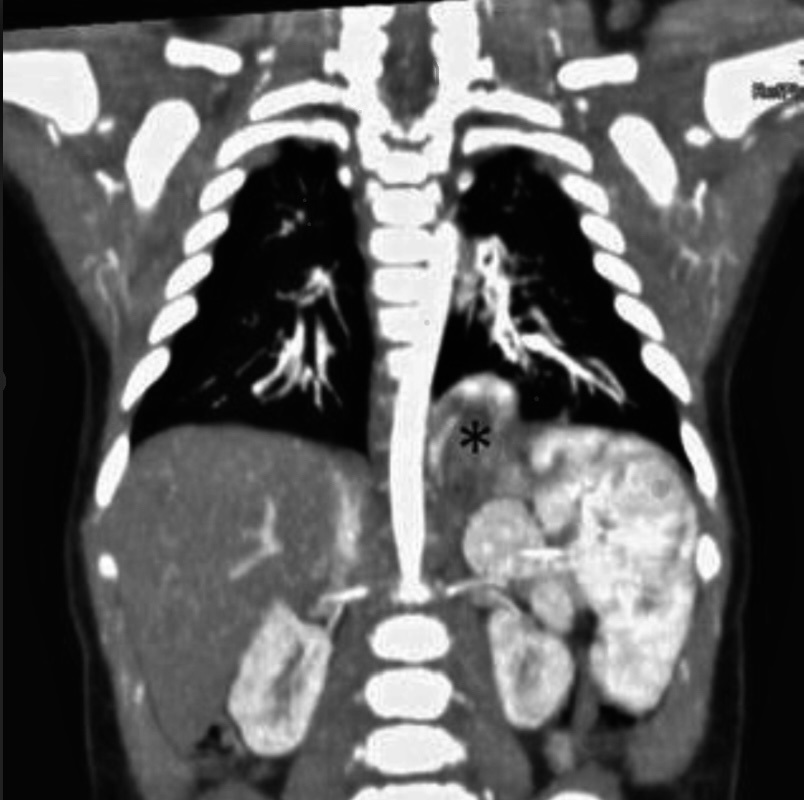

Figure 1

(A) Prenatal MRI is showing an expansive lesion located in the posterior mediastinum. (B) Postnatal computed tomography image showing the lesion located at the level of T8 vertebra (*), supplied by an arterial vessel, coming from the celiac trunk. (C) Macroscopic finding.

A full-term male infant was referred to our hospital for an anomalous thoracic mass found during fetal ultrasonography. At 32 weeks of gestation, a fetal MRI confirmed the presence of an expansive lesion located in the posterior mediastinum, measuring 41 x 32 x 27 mm. No distinct vascular supply was detected. At birth, the baby was shifted to our neonatal intensive care unit, spontaneously breathing with stable vitals. No associated anomalies were identified. At 11 days of life, angio-MRI and a thoracoabdominal CT scan showed a hiatal hernia with the gastric fundus sliding in the thorax. The previously described lesion was located at the level of the T8 vertebra, anterior to the thoracic aorta, extending through the diaphragm's esophageal hiatus until a retro-gastric position. It appeared to be supplied by an arterial vessel coming from the celiac trunk.

Barium X-ray excluded bronchopulmonary foregut malformation and confirmed the hiatal hernia with gastro-oesophageal reflux. Early surgery was planned in order to define the nature of the lesion. The parenchymatous mass was located in the abdomen, in the inter-aortocaval region, supplied by an arterial vessel from the left gastric artery. It was excised "en bloc" via an open approach. The wide defect of the esophageal hiatus was repaired through a hiatoplasty, and a Nissen fundoplication was performed. Gross examination and histopathological findings were consistent with the diagnosis of pulmonary sequestration (Fig. 1). The patient was discharged on the tenth postoperative day. Follow-up at six months showed no complications.